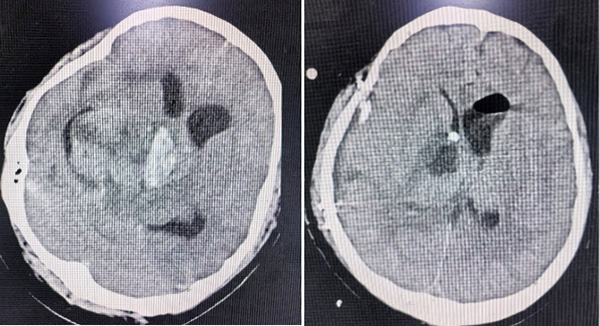

兩名患者情況類似,均為顱內(nèi)巨大腫瘤伴腫瘤卒中,出現(xiàn)因腦干受壓,瞳孔增大,如果沒有迅速得到處理,患者一般會在幾小時內(nèi)陷入昏迷,造成死亡。面對這種緊急情況,張玉琪教授接到值班醫(yī)生匯報,沒有絲毫猶豫,立即組織團(tuán)隊進(jìn)行術(shù)前準(zhǔn)備,并迅速投入到緊張的手術(shù)中,張玉琪教授以高超的醫(yī)術(shù)和團(tuán)隊成員、麻醉科的鼎力配合,成功為兩名患者完成了急診手術(shù),最終兩名患者均轉(zhuǎn)危為安。

患者1 手術(shù)前后腦部CT影像

患者2 手術(shù)前后腦部CT影像